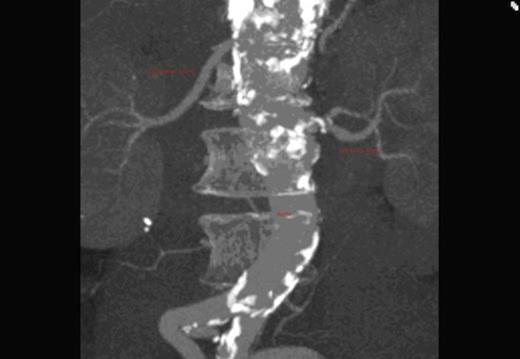

We present a rare case of an ectopic main right renal artery originating as part of the coeliac axis. Renal arteries are usually paired vessels which originate directly from the aorta to supply each kidney. Variations in their origin and numbers have been reported by many authors. However, there has only been one previous report of a left main renal artery arising from the coeliac axis in the medical literature, in 1980, seen during angiography. We believe we have the first CT angiographic evidence of such anatomy. This important aberrant anatomy must be noted not only for its rarity but also for its implications in the field of transplant surgery and interventional radiology. There will be more similar reports as non-invasive imaging is being used ever more frequently.

A CT scan revealed an aneurysmal distal thoracic aorta measuring 40mm and 49mm at the level of the diaphragm and of normal calibre at the left renal artery. The right renal artery very interestingly had its origin from the coeliac axis with no significant renal artery disease and the left renal artery showed calcific disease with post-stenotic dilatation at its ostium from the aorta. There were also no accessory renal vessels noted.

Therefore, we have only the second documented single main ectopic renal artery originating directly from the coeliac axis. Furthermore we are the only ones to have CT angiographic evidence of the above.